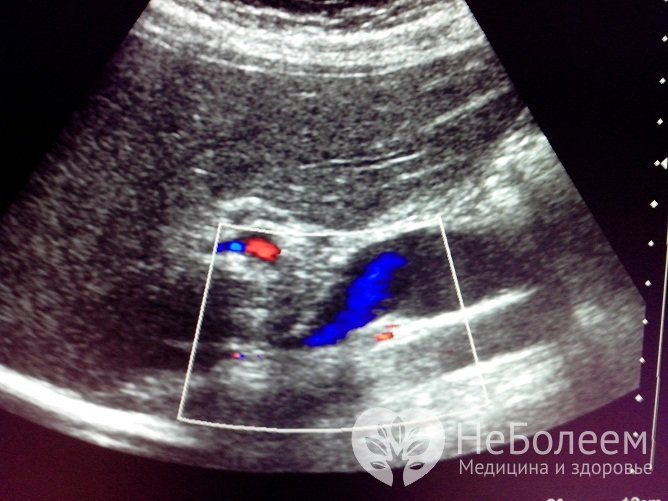

Для определения размеров и точной локализации паразитарной опухоли в печени выполняют допплерографию, УЗИ печени, рентгенографию брюшной полости; высокой диагностической ценностью обладает компьютерная томография. В ряде случаев возникает необходимость в проведении диагностической лапароскопии и сцинтиграфии печени.

Альвеококкоз на УЗИ-диагностикеДля выявления возможного наличия метастических опухолей осуществляют УЗИ органов брюшной полости, МРТ головного мозга, рентгенографию грудной клетки.